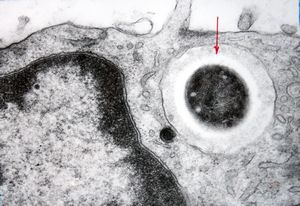

cytomegalovirus - pneumonia